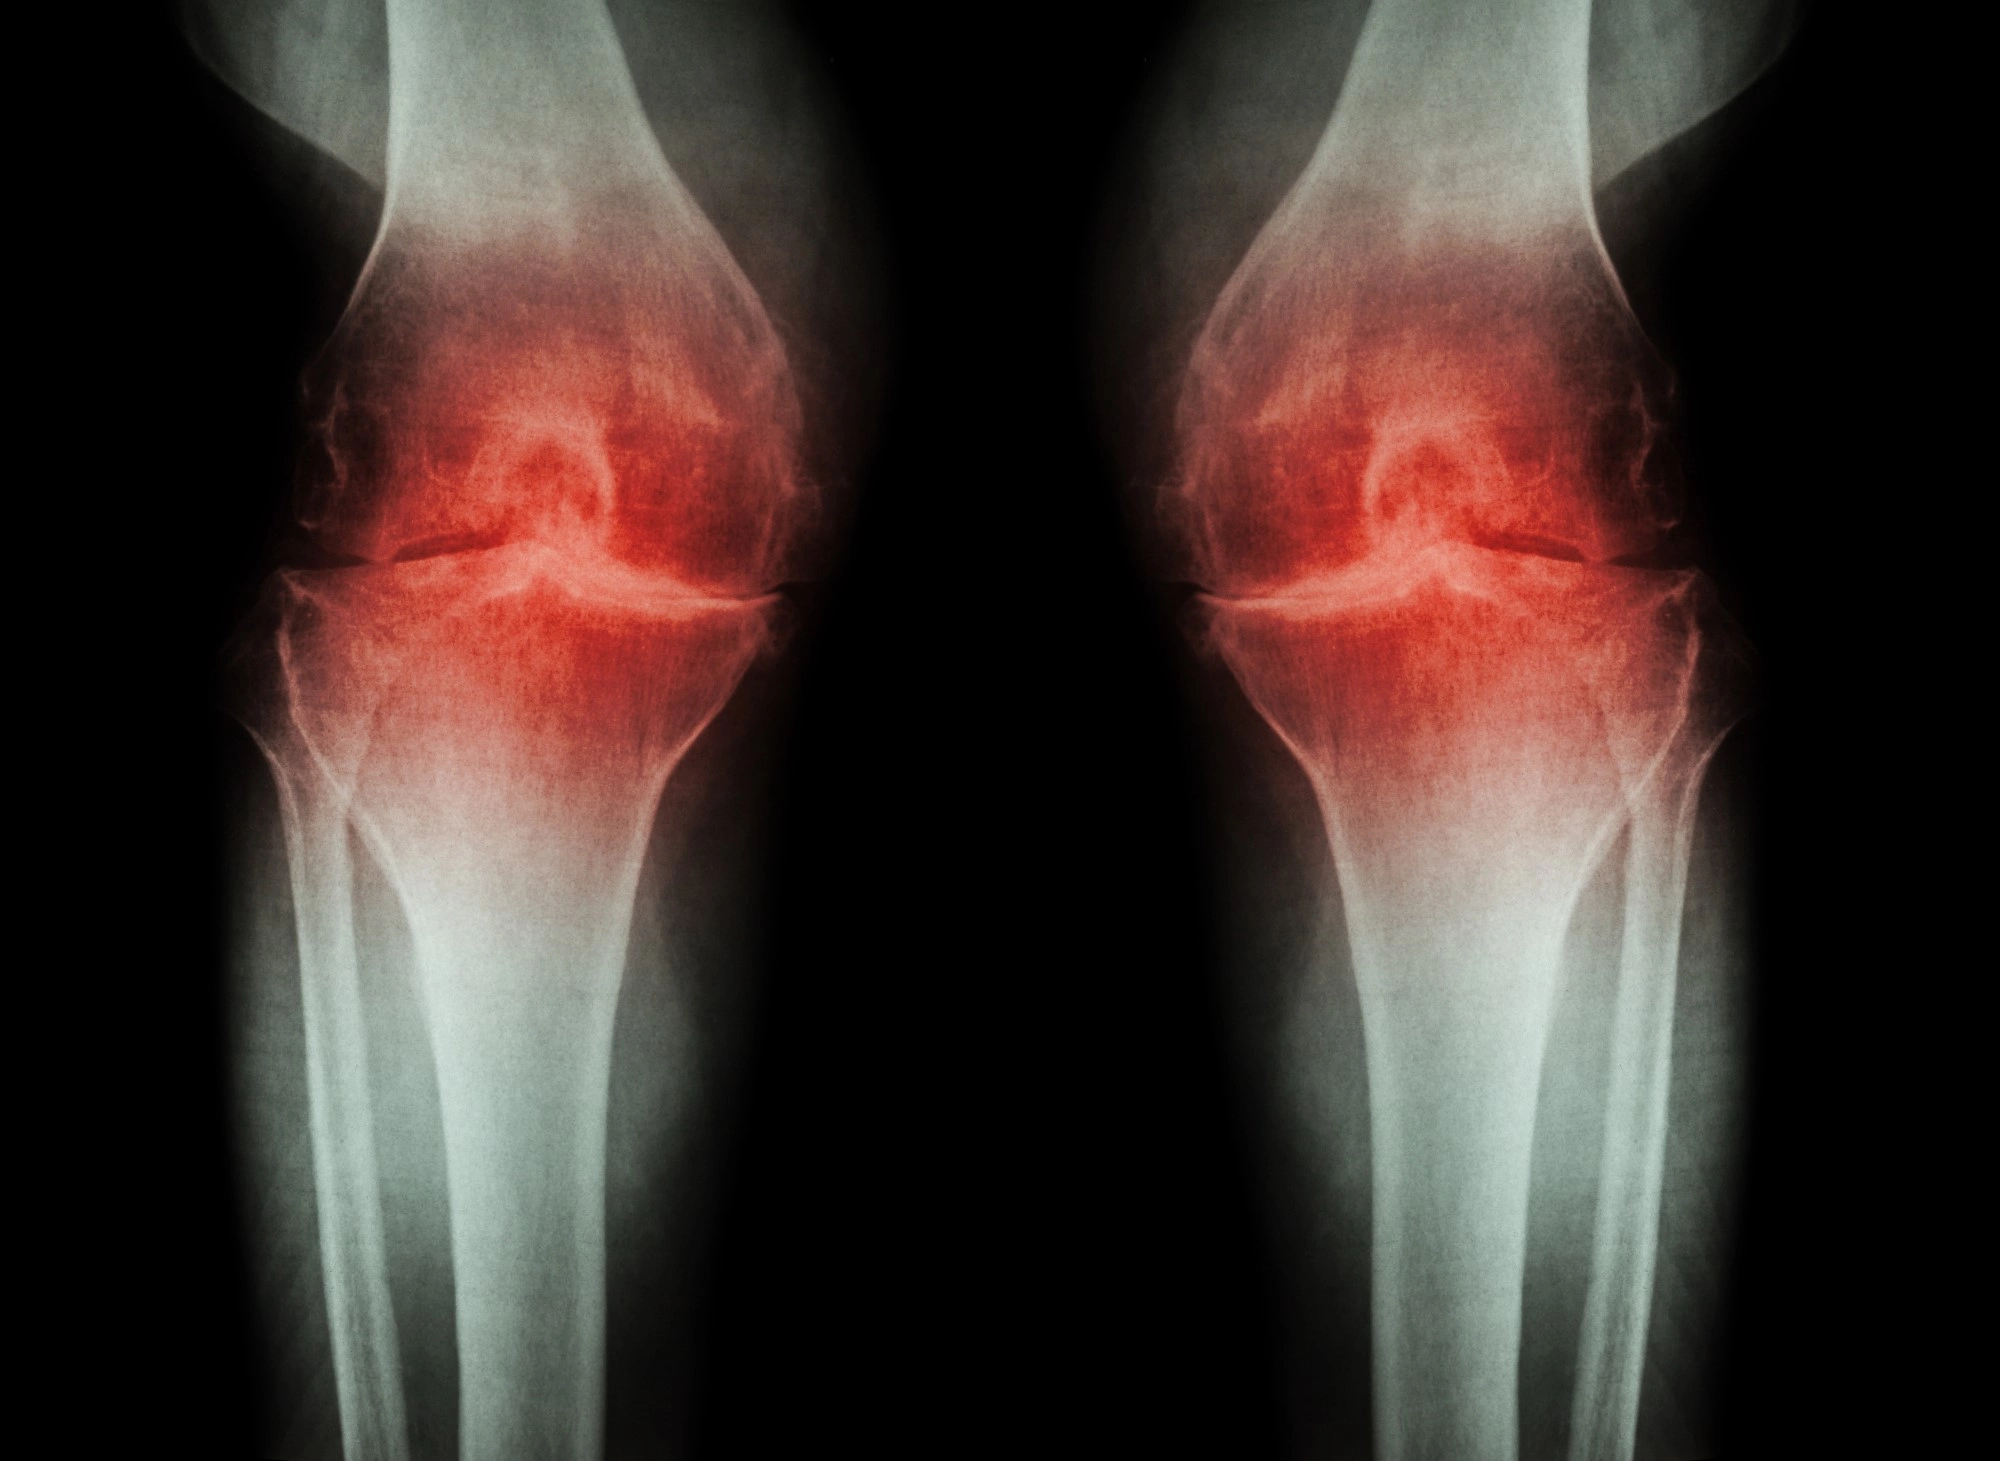

Остеоартрит – это патологическое состояние организма, при котором поражаются суставы. Проявляется заболевание воспалением, нарушением подвижности и деформацией пораженного сустава. Остеоартроз может протекать в острой или хронической форме. Терапия заболевания консервативная и направлена на замедление разрушения суставных поверхностей, уменьшение боли, улучшение работы суставов. При тяжелой степени болезни, когда консервативное лечение не помогает, пациенту может быть рекомендована операция по эндопротезированию сустава.

Медицинский диагноз ставит врач на основании данных анамнеза, опроса, осмотра пациента, а также результатов инструментальных исследований. Наиболее информативными считаются такие методы, как рентгенография, МРТ, УЗИ, КТ.